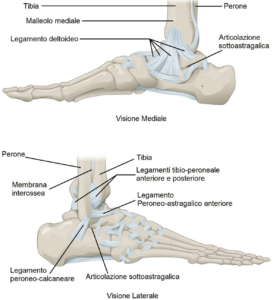

La caviglia è un articolazione formata da tre ossa (astragalo, tibia e perone) che sono connesse tra di loro mediante dei legamenti.

Nella parte mediale (più interna) troviamo il legamento deltoideo, formato da quattro legamenti che uniscono la tibia con altre ossa; questi legamenti sono il tibio-astragalico anteriore, tibio-astragalico posteriore, tibio-calcaneare e tibio-navicolare. Questi ultimi due legamenti connettono la tibia con due ossa del tarso (piede) ovvero il calcagno e l’osso navicolare.

Nella parte laterale invece troviamo i legamenti peroneo-astragalico anteriore e il peroneo-astragalico posteriore, che connettono il perone con l’astragalo, e il legamento peroneo-calcaneare, che mette in rapporto il perone con il calcagno.

Sono presenti inoltre due legamenti che collegano nella parte inferiore la tibia e il perone, ovvero il legamento tibio-peroneale anteriore e il legamento tibio-peroneale posteriore.